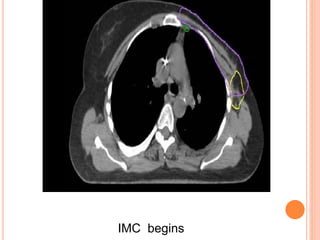

REGIONAL NODAL CONTOURING

IMC begins